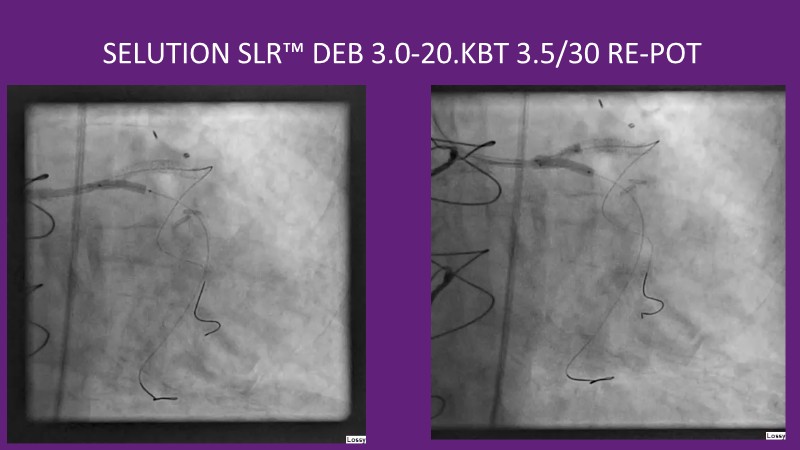

This EuroPCR 2025 session provides a comprehensive overview of drug-eluting balloons (DEBs) and their growing role in percutaneous coronary intervention (PCI). Gain a clear understanding of the clinical evidence and rationale supporting DEBs, including how these devices minimize metal implantation and effectively treat both standard and complex coronary lesions. The session highlights the mechanistic advantages of drug selection and sustained drug release technologies, with a focus on the SELUTION SLR DEB. Clinical updates include the LOVE-DEB study advocating a DEB-first approach in large vessel coronary artery disease, real-world performance data from the Malaysian registry, and practical case examples illustrating the transition to DEB-based PCI in clinical practice.